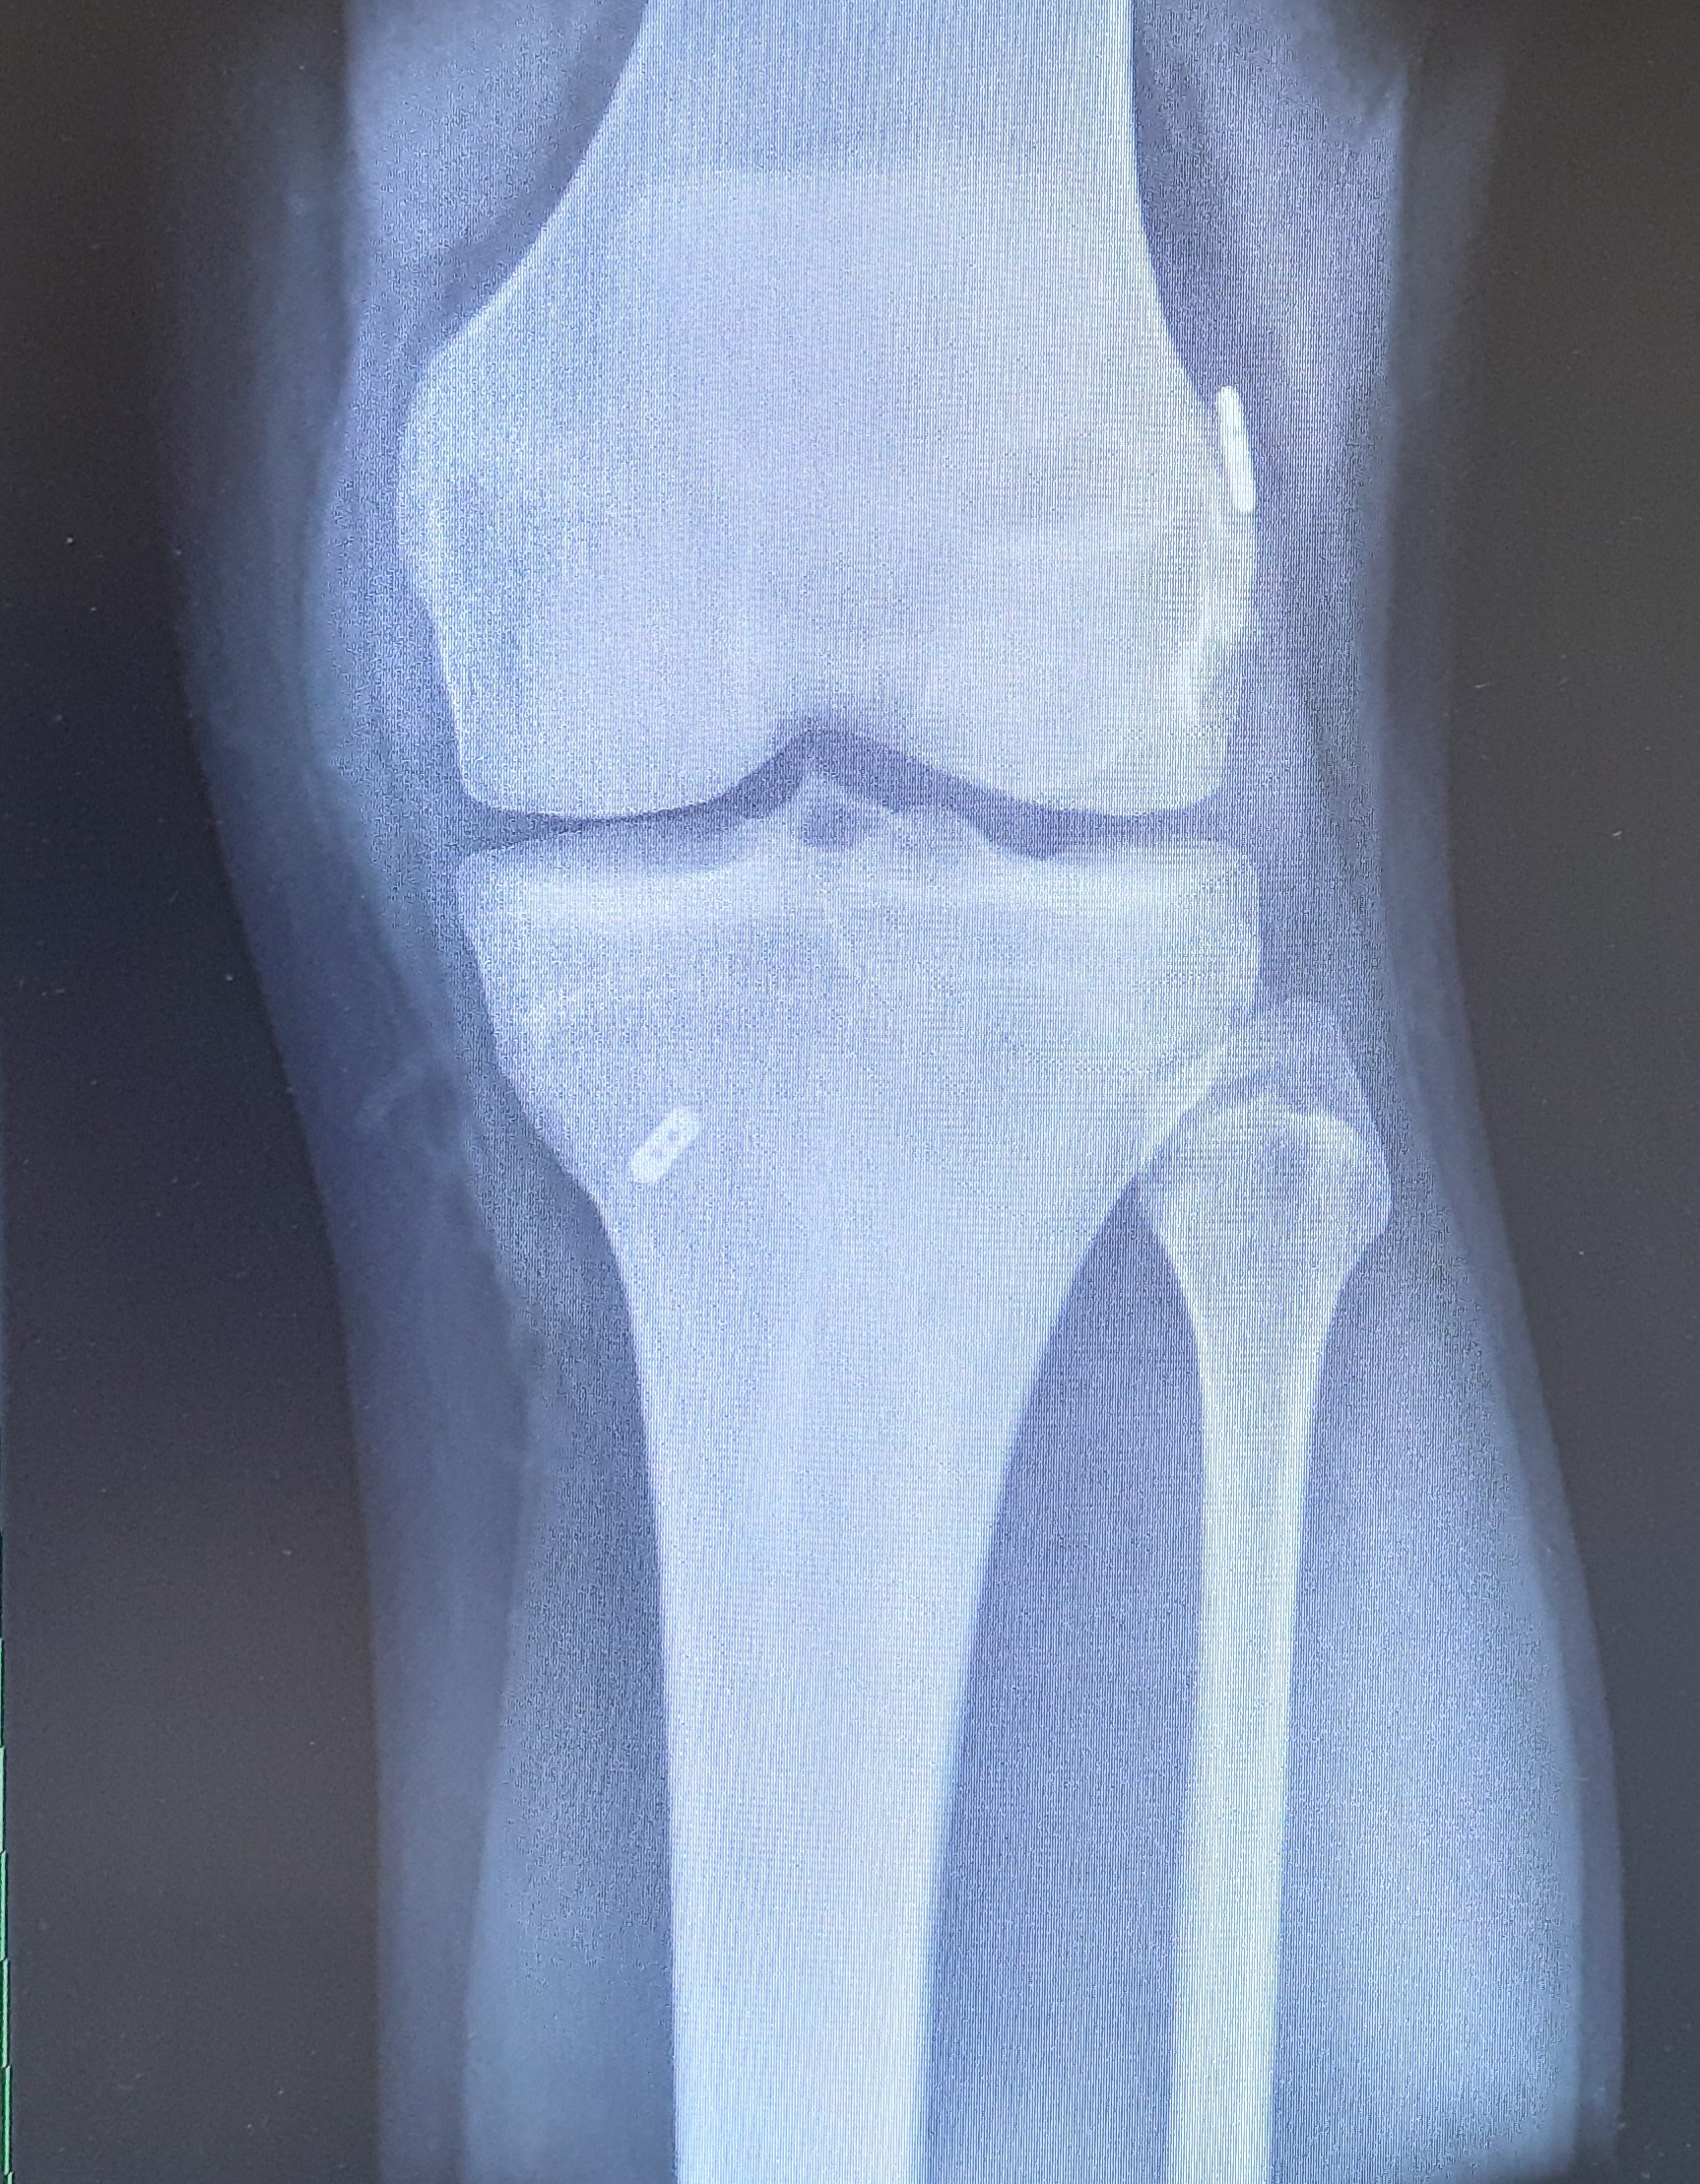

Klinik und Diagnose

Typisch sind belastungsabhängige Schmerzen, anfangs sog. Anlaufschmerzen, später auch Beschwerden in Ruhe. Schließlich kommt es schmerzbedingt zu einer massiven Einschränkung der Gehstrecke. Zudem kann es auch immer wieder zu Ergussbildungen kommen.

Klinisch erfolgt die Beurteilung durch die Anamnese und die Untersuchung. Schmerzen beim Gehen als auch lokale Druckschmerzen über dem Gelenksspalt können festgestellt werden. Weiters können Achsfehlstellungen beurteilt werden sowie Schwellung, Überwärmung, knirschende Geräusche beim Durchbewegen des Gelenkes oder Bandlockerungen aufgrund der Arthrose und Fehlstellung.

Standardmäßig werden Röntgenaufnahmen in zwei Ebenen sowie eine Ganzbeinstandaufnahme durchgeführt. Im Anschluss kann bei noch unklarem Knorpelzustand eine MRT-Untersuchung zur besseren Beurteilung des Schädigungsgrades des Knorpels erfolgen.